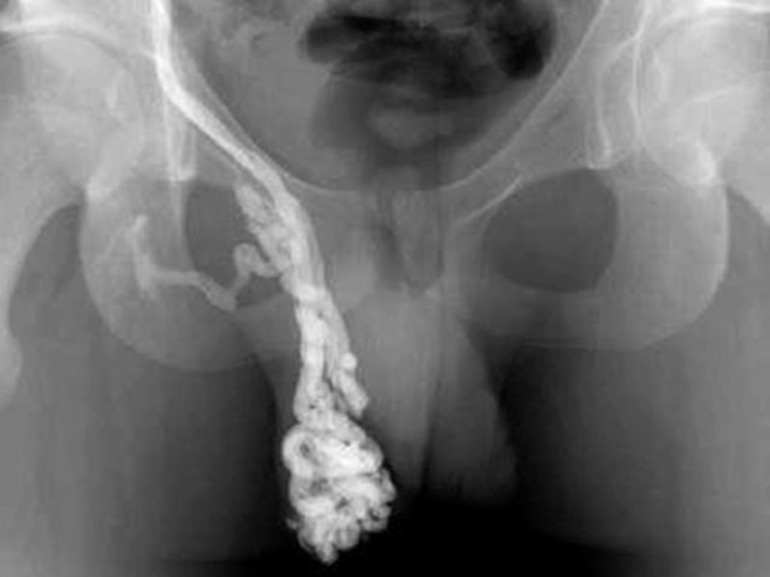

- венография (изучение работы вен);